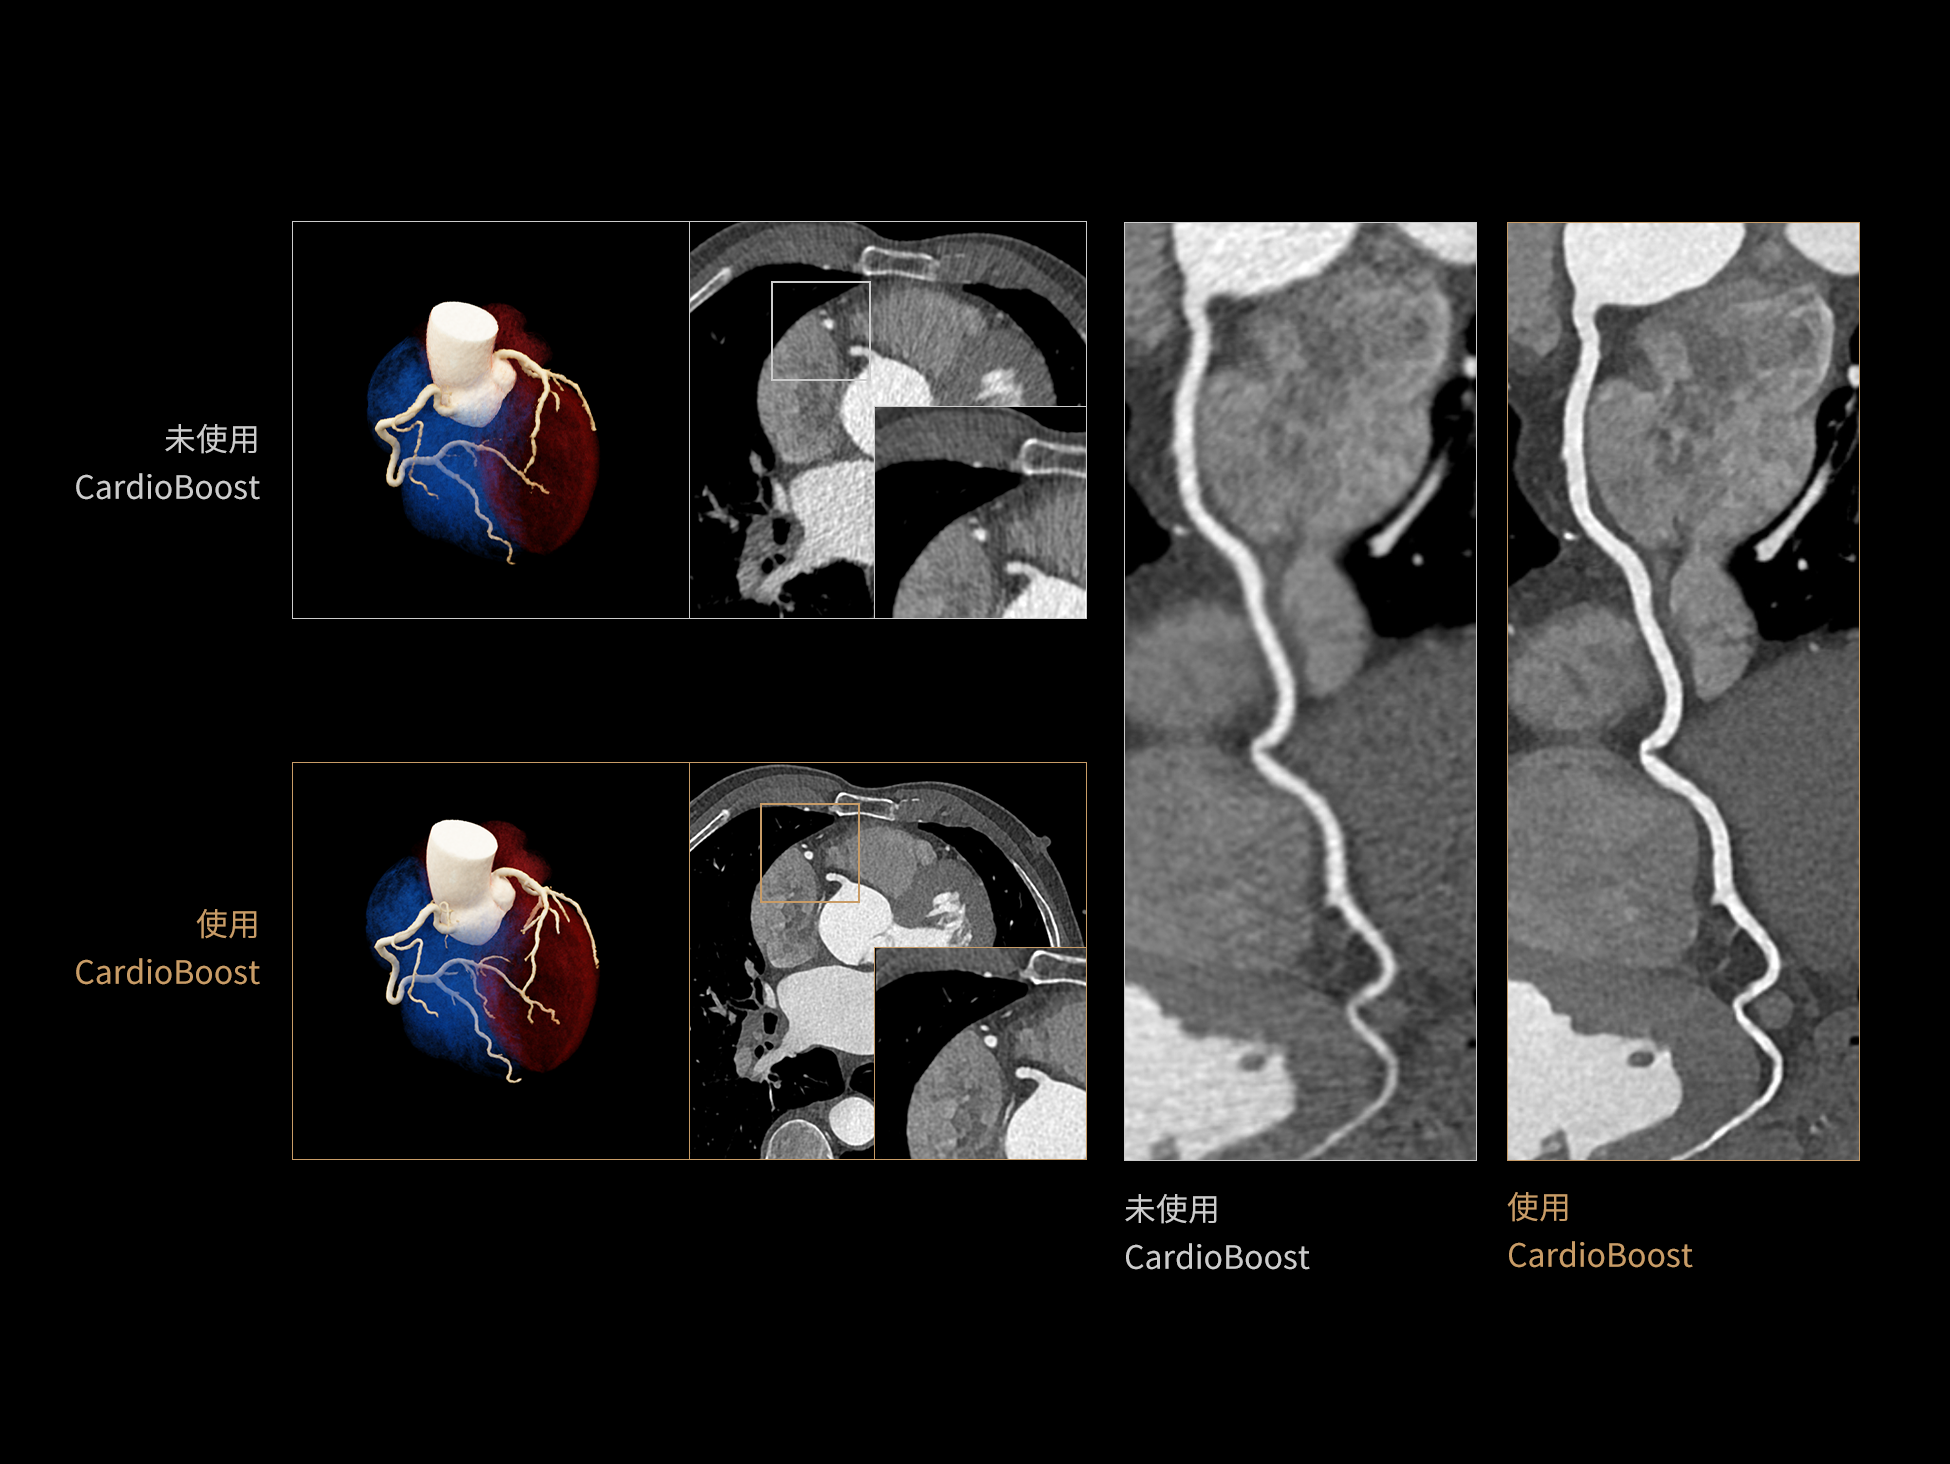

CardioBoost:专属网络设计,重塑心脏影像表现

uCT 868 搭载联影最新一代 uSense 人工智能平台,将智能化深度融入 CT 扫描全流程,从感知细微生理运动到精细结构探测,再到多场景诊疗优化。以 AI 为核心驱动力,uSense 重塑成像各环节,打造高效、高清的智慧扫查体验。在心脏成像领域,uSense 结合宽体探测器、心脏专研AI重建算法与AI冠脉运动追焦技术,在保持低剂量的同时,有效抑制运动伪影,精准呈现软斑块、混合型斑块及支架细节,助力冠脉成像惠及更多患者。针对多科室疾病临床应用场景,uSense 平台提供全方位的智能解决方案:包括头部运动伪影智能校正、金属植入物伪影抑制、扫描视野扩展等先进算法。这些创新技术使 uCT 868 能够构建覆盖全场景的智能诊疗体系,持续拓展 AI 赋能医学影像的边界。

作为高端CT解决方案平台,uCT 868 凭借高速扫描能力、宽体探测器、AI驱动重建算法和智能工作流,能够从容应对上述急症场景下的多部位、多模式联合检查需求。不论是冠脉、主动脉与肺动脉的一站式成像,还是卒中的快速识别,亦或是全身创伤评估中的快速定位与精细结构显示,uCT 868 均能以高速、清晰、低剂量的成像表现,助力临床在关键时刻做出快速而准确的诊断判断,赢得宝贵救治时间。